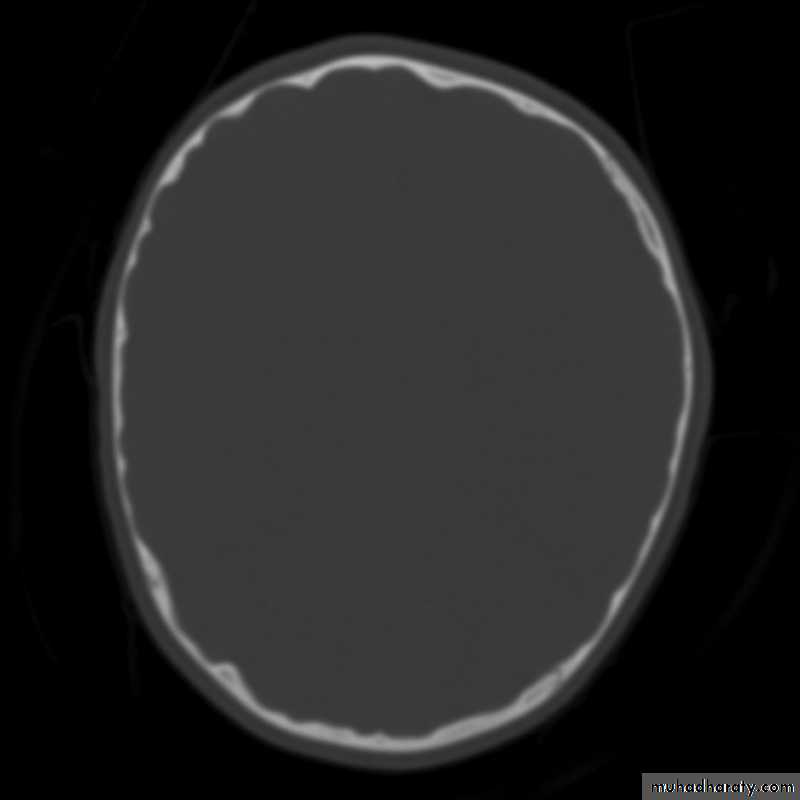

Skull X-ray findings in increased intracranial pressure

• Sutural separation in children.

• ‘Copper-beating’ marking of the cranial vault.

• Thinning of dorsum sellae.

• Erosion of the posterior clinoid process.

Copper-beating’ marking

Neurosurgery